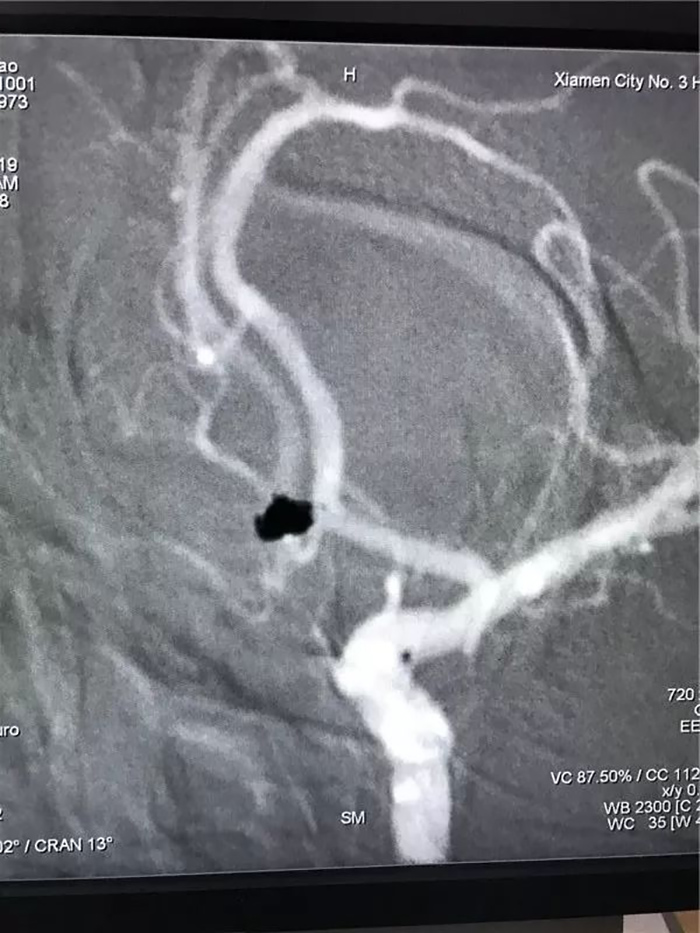

颅内动脉瘤被神经外科医生称为

“颅内不定时炸弹”,

一旦破裂病情极其凶险,

致死、致残率高,

且首次破裂后再破裂风险高,

二次破裂死亡率接近80%,

需紧急急诊手术介入栓塞

或开颅夹闭动脉瘤。

对患者吴先生紧急行“颅内动脉瘤栓塞术”。

小腿到腹部的伤口还没愈合,身上又穿着重达一二十斤重的铅衣做手术……这场手术结束后,陈锋龙发觉,尚未愈合的伤口又渗液加重了。手术顺利完成,动脉瘤致密栓塞,术后患者清醒拔管。接下来的11月22日上午及11月23日晚上,陈锋龙医生又独自完成了两台急性脑梗死介入取栓手术:其中一台术前静脉溶栓术中脑血管造影证实闭塞的血管已再通;另一台一侧颈内动脉及大脑中、大脑前闭塞经取栓,完全开通血管。做完这几台手术,团队成员学习归来了,陈锋龙才继续在家休养。